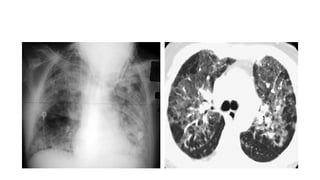

• A chest x-ray (A) shows

bilateral non-specific diffuse

interstitial coarsening and a

cyst in the right lower lobe

(arrow).

• A coronal reconstruction of a

CT scan (B) confirms the

presence of cysts in the right

lower lobe and left upper

lobe (arrows).

• An axial CT scan (C) shows

extensive bibasilar cystic

changes (dashed arrow)

and interstitial thickening

(arrow) with changes in the

left pleural space (arrowhead)

following wedge biopsy.

• A diagnosis of LIP was

confirmed by biopsy.

• A chestx-ray (A) shows bilateral non-specific diffuse interstitial coarsening and a cyst in the right lower lobe (arrow). • A coronal reconstruction of a CT scan (B) confirms the presence of cysts in the right lower lobe and left upper lobe (arrows). • An axial CT scan (C) shows extensive bibasilar cystic changes (dashed arrow) and interstitial thickening (arrow) with changes in the left pleural space (arrowhead) following wedge biopsy. • A diagnosis of LIP was confirmed by biopsy.